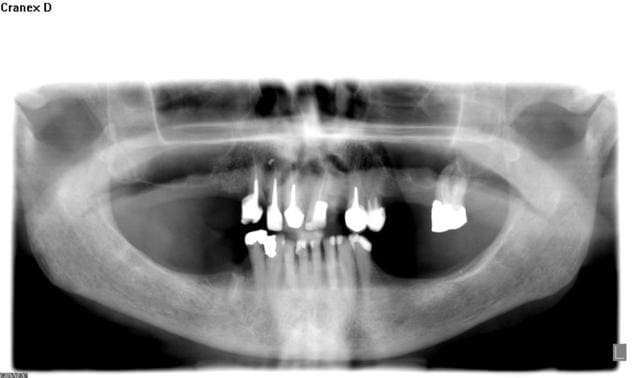

Voilà je vous fournis l'OPT et le CRO.

Avant que tout le monde ne rentre dans le débat de savoir si c'est un acte très complexe ou pas, je tiens à vous rappeler que le débat n'est pas là.

On peut considérer cette racine sur un plan clinique comme incluse ou enclavée, la muqueuse était totalement refermée par dessus.

Ce n'est pas le geste chirurgical le plus difficile mais cela n'enlève rien à la cotation et à l'interprétation de la CDC.